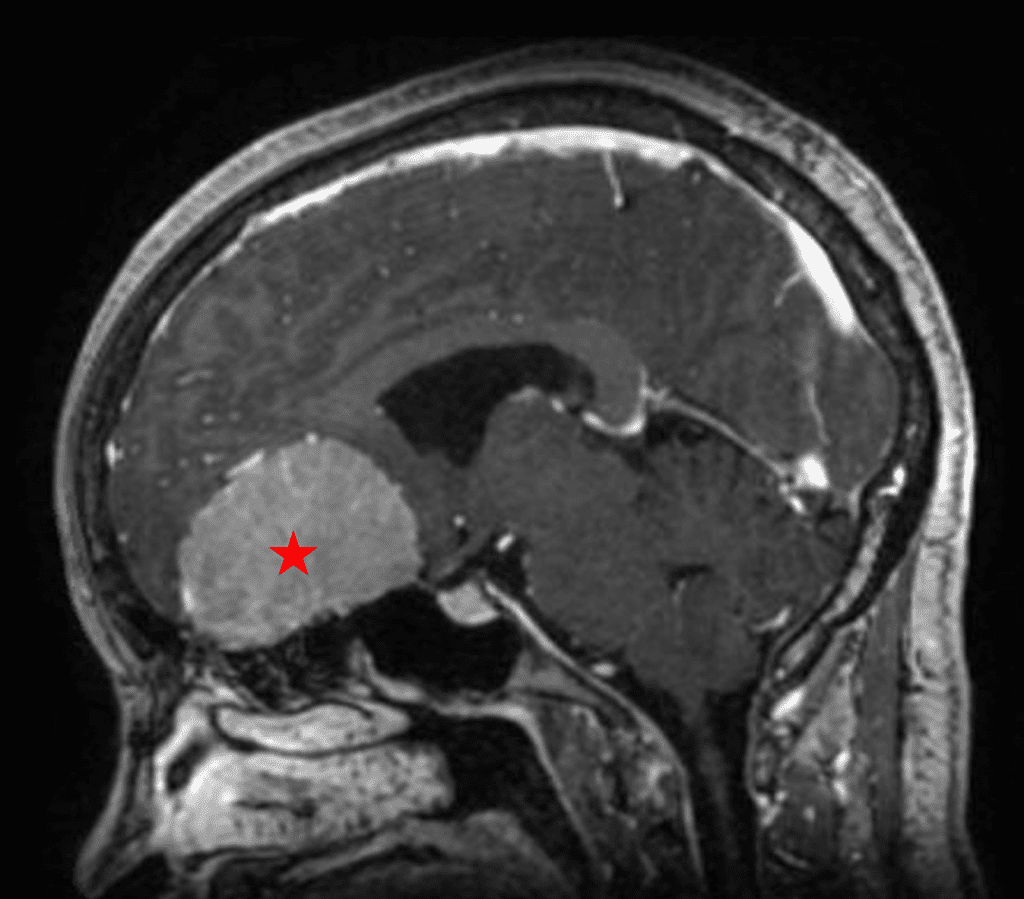

This is a 49-year-old otherwise healthy female who presented with bifrontal and retro-orbital headaches, behavioral changes, and forgetfulness. Symptoms have been progressively worsening over the past month. Her neurologic exam revealed a pronator drift, otherwise was unremarkable. MRI brain demonstrated a large extra-axial homogeneously enhancing mass of the anterior cranial fossa, resulting in significant mass effect and vasogenic edema (Figure 1a and 2a). Imaging was most consistent with a planum sphenoidale meningioma. She was referred to Dr. Xavier Gaudin for neurosurgical evaluation.

Figure 1a – Preoperative MRI demonstrating an extra-axial enhancing mass of the anterior cranial fossa.

She was started on high-dose steroid and antiseizure prophylactic medicine. Surgical intervention was offered for mass effect, symptomatic relief, neurologic preservation, and histopathologic diagnosis. Dr. Gaudin performed a bifrontal craniotomy with complete resection of neoplasm through an interhemispheric and subfrontal approach. Postoperative imaging demonstrated a gross total resection without residual tumor and resolution of mass effect (Figure 1b and 2b). Intraoperative pathology was consistent with meningioma, WHO grade 1. She recovered very well, and was discharged home on postoperative day 3. On her follow-up outpatient visit, her preoperative symptoms had fully resolved, and her olfactory sense was maintained.